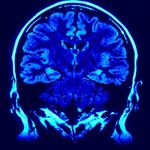

“As we get older, we all lose a little gray-matter volume and white-matter integrity, but in alcoholics, those areas break down more quickly. It looks like accelerated aging,” says Edith Sullivan, a professor of psychiatry and behavioral science at Stanford University.

Modern brain scanning technology shows that excessive alcohol use over long periods of time can actually damage white-matter fibers that connect the various areas of the brain together, according to the article. It can also alter brain structure, negatively affecting gray-matter cells responsible for:

Brain scanning allows doctors to diagnose “alcohol-induced neurocognitive disorder” and “alcohol-related dementia.” Researchers point out there is no way of knowing the threshold that, when crossed, could result in the aforementioned health problems, the article reports. Alcohol affects everyone differently, and there are a number of factors to consider when determining the effects of excessive use, such as: